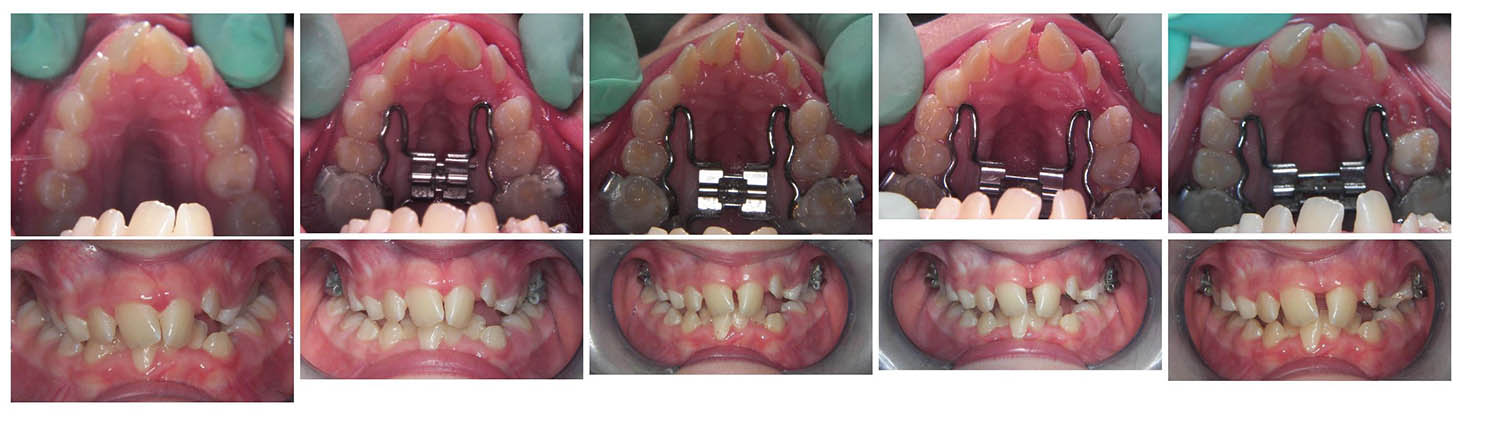

U sljedećim galerijama možete vidjeti primjere upotrebe Hyraxa:

2. primjer